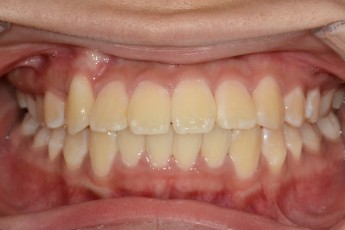

Before

After